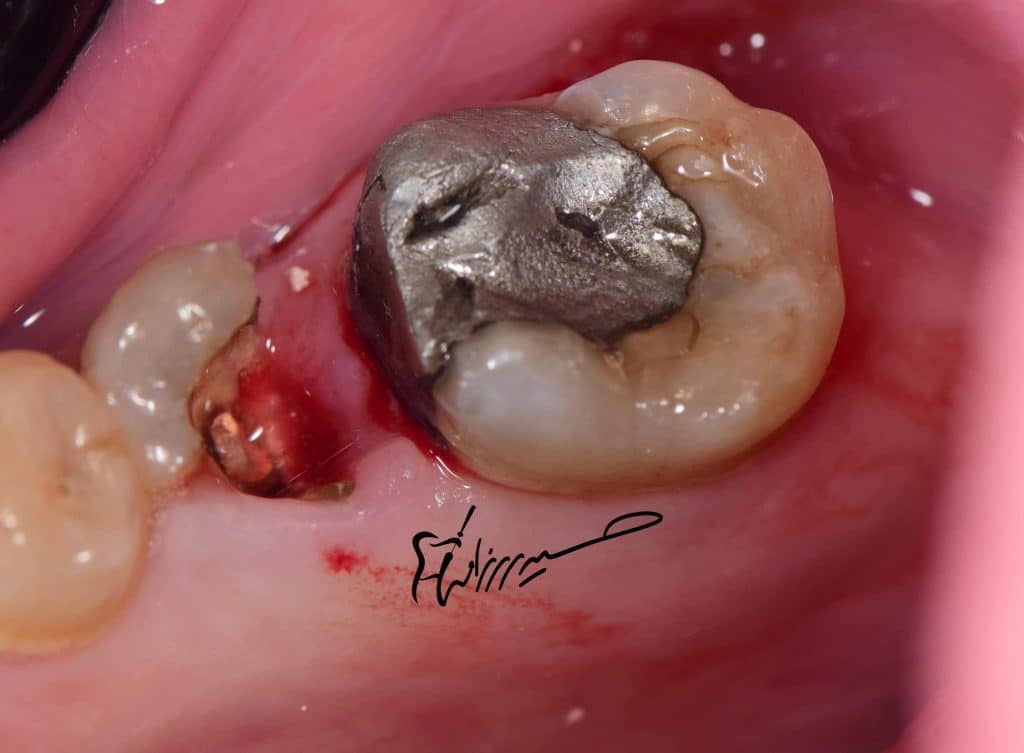

The tooth with large defective amalgam restoration ,

After removing the old restoration,

the tooth was dying ! And the margin level below the bone level!

Fractured premolar with defective amalgam restoration and contact of both premolar and 1st molar .

Remove the old defective filling from tooth n.35 and also no.36 (overhanged!).